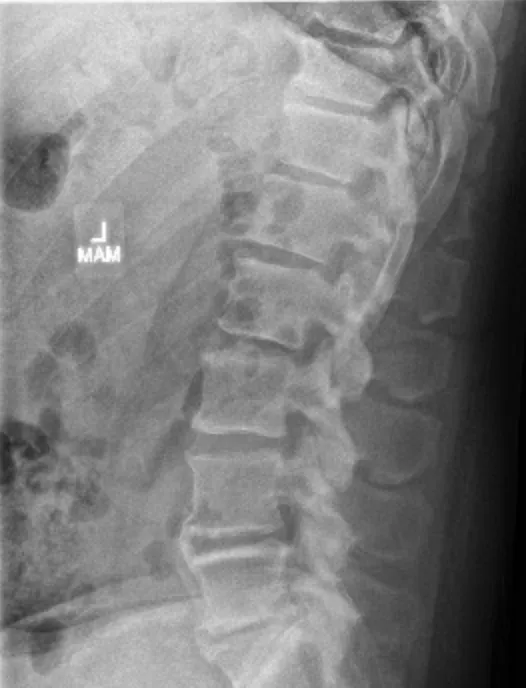

Degenerative disc disease, loss of disc height, disc bulges/herniations, and nerve compression are common findings in patients who may benefit from decompression-based care.

Spinal decompression is a controlled, motorized form of traction designed to reduce pressure inside damaged spinal discs. By creating cycles of gentle distraction and relaxation, decompression can help improve disc hydration and reduce mechanical stress on irritated nerves.